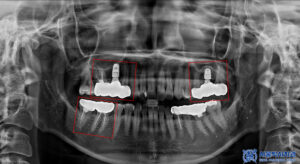

파노라마 촬영으로

전체 상태를 먼저 확인했습니다.

다만 크라운은 방사선 불투과성이 있어

내부 평가가 제한되므로,

정밀 엑스레이를 추가로 촬영해

보철물 하방 상태를 점검했습니다.

그 결과, 브릿지 아래쪽에

우식이 진행된 것이 확인되었습니다.